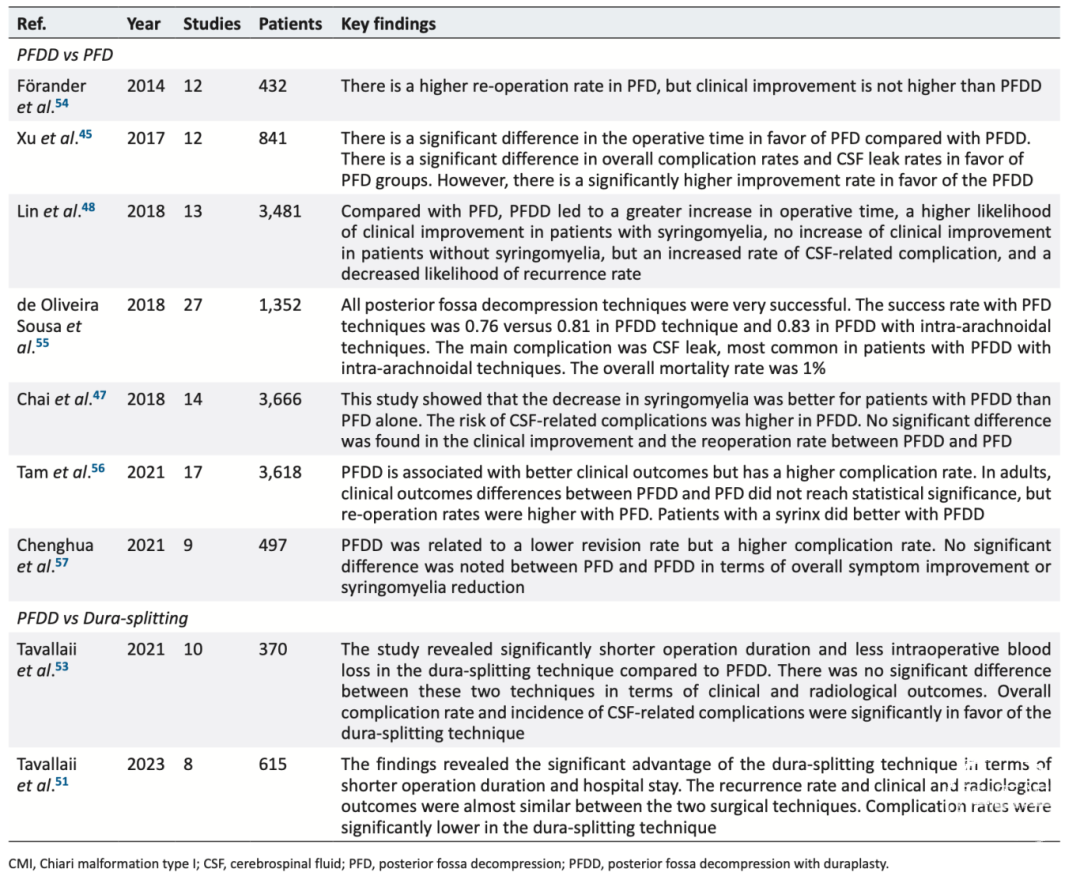

为了比较这三种手术方式,我们总结了近期相关的系统综述和荟萃分析研究,其结果见表1。

● 在临床症状缓解、影像学改善及再手术率方面,PFDD优于硬脑膜分层术,而硬脑膜分层术又优于单纯PFD。

● 在手术并发症方面,PFDD的脑脊液相关并发症高于其他两种术式。

● 在住院时间、手术时长及术中出血量方面,PFDD亦高于其他两种方法。

对于合并脊髓空洞症的CMI患者,我们倾向优先选用PFDD术。这一选择原因:1)小脑扁桃体下疝的慢性压迫刺激常导致颅颈交界区的蛛网膜、神经和血管粘连,如不进行松解,可能难以缓解脑脊液循环障碍;2)显微技术和硬膜修补材料的进步可减少脑脊液相关并发症。

表1. 涉及PFD、PFDD和PFD联合硬脑膜分层术的系统评价和荟萃分析的总结